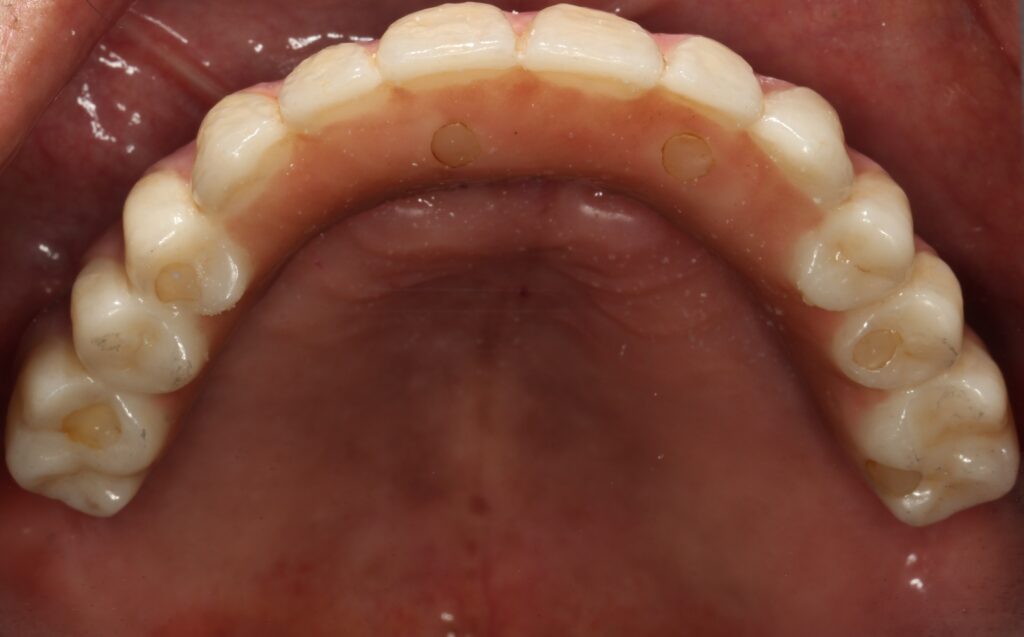

A selection of full arch fixed implant bridge patients after 5 years of wear